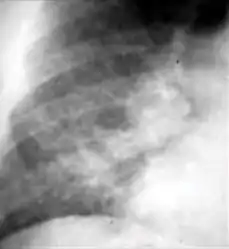

Chest x-ray showing coarse reticulonodular densities on the lower right lung of post-primary pulmonary TB.

7. Other - Any other finding suggestive of active TB, such as miliary TB. Miliary findings are nodules of millet size (1 to 2 millimeters) distributed throughout the parenchyma.